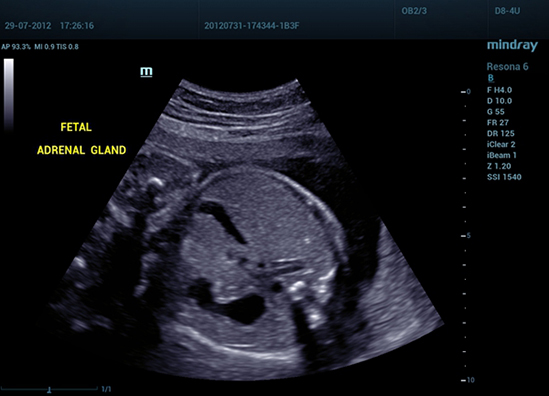

• 05 Fetal Adrenal Gland

Надпочечник плода